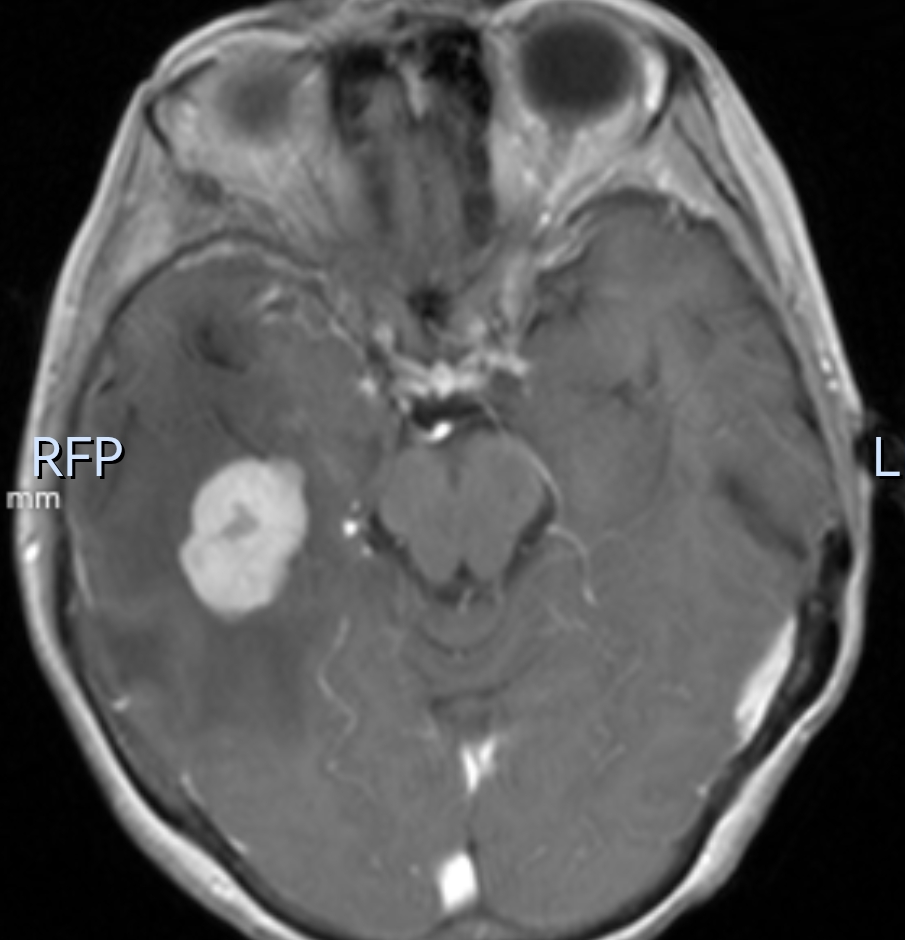

61岁的患者王女士因头痛10余天就诊外院,经头颅核磁共振检查显示颅内多发结节状占位,分布于双侧大脑半球及基底节区等部位,呈结节样强化,周围伴有明显水肿带。上述的描述与常见的“颅内多发转移瘤”(如肺癌、乳腺癌等实体瘤转移至脑部)高度相似,外院初步诊断为转移瘤,建议进一步寻找原发肿瘤灶。

患者核磁共振检查